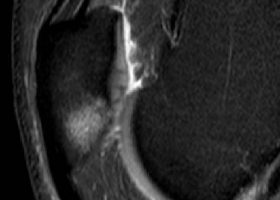

Speichen-Pseudarthrose, verheilte Elle